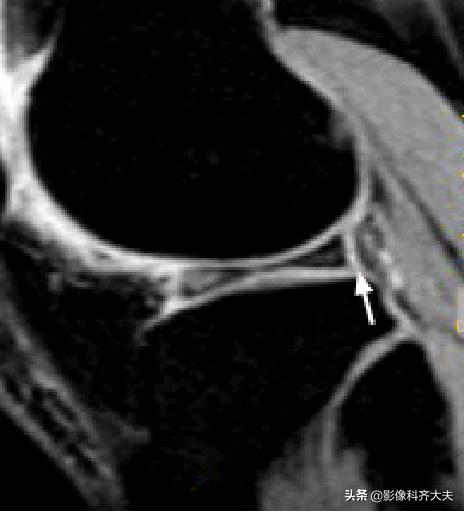

容易误诊为半月板损伤的正常解剖结构

膝横韧带: